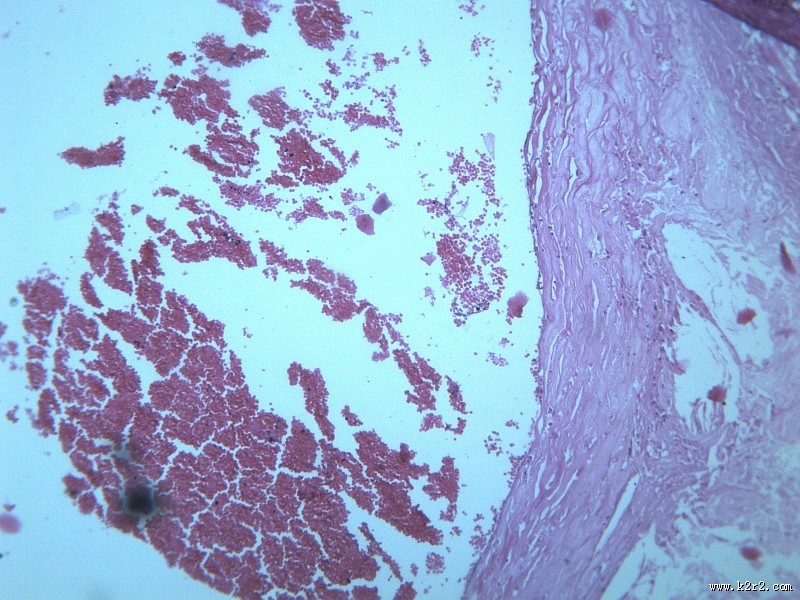

动脉粥样硬化 - 第7张